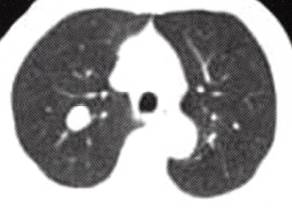

图1肺错构瘤

B

B.CT平扫肺窗示右肺上叶孤立结节,无分叶,边缘光整,周围肺野清晰;

1)周围型:

(1)病灶直径多<2.5 cm,边缘光滑,可浅分叶。 (2)病灶密度不均匀,可见短条状钙化,典型征象为“爆米花样”钙化,部分见脂肪密度影。 (3)增强扫描病灶无明显强化。 2)中央型: (1)支气管腔内结节,边缘光整,可见钙化。 (2)附着处支气管壁无侵蚀增厚。 (3)远端支气管阻塞性肺炎和/或肺不张改变。 4.MRI表现: 周围型结节显示信号不均勻,脂肪成分显示优于CT,可确诊。影像学检查显示肺周围境界光整的孤立性结节,见有“爆米花样”钙化或脂肪组织即可确诊。 【分析思路】 诊断依据: 1.患者为男性,63岁。无症状,偶然发现。 2.右肺孤立性结节,边缘光滑,无分叶,结节内多个点条状钙化,有脂肪样密度影,增强扫描病灶无明显强化。 3.无肺门、纵隔淋巴结增大及胸腔积液。 鉴别诊断: 1.周围型肺癌:①多为大于3 cm的肿块。②结节型多边缘毛糙,见“短毛刺征”“分叶征”。③病灶密度多不均勻,可见“空泡征”。④偶见点状钙化。增强多为明显强化。⑤本例结节灶未见肺癌常见征象,也未见肺门及纵隔淋巴结肿大、胸腔积液,所以不符合肺癌影像学表现。 2.结核球:①多位于两上肺。②结节灶单发多见,边缘锐利,无分叶,多有钙化等良性征象。③结核结节周围常见“卫星灶”,结节中央干酪样坏死密度低,钙化为点簇、层环样表现,增强如有强化则多呈环状强化。④本例结节内钙化形态呈短条样且见脂肪密度影,病灶周围肺野清晰,所以不支持结核球诊断。 3.肺内其他良性肿瘤:①与此例类似征象如:结节灶光整,无分叶。②无此例结节灶内所见钙化形态、数量和脂肪样密度征象,所以不考虑其他罕见良性肿瘤诊断。 4.肺动静脉瘘:①与此例类似征象如:孤立结节、边界光整、无分叶。②动静脉瘘增强扫描可见特征性的病灶明显强化及引流血管影征象,所以不符。